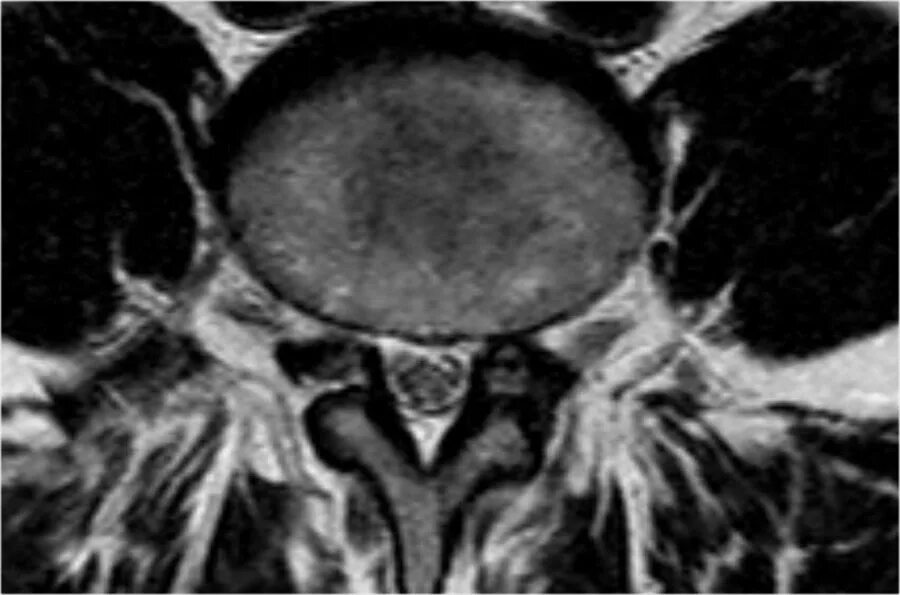

Грыжа диска мрт